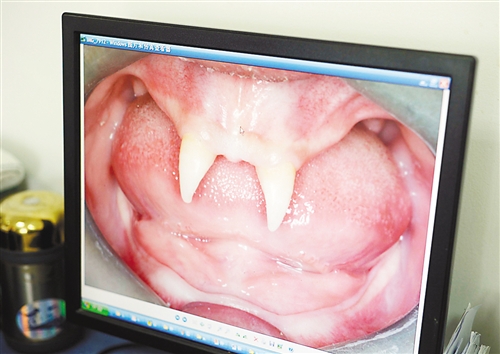

12月18日,16歲的張成(化名)從小到大,只有上顎部分有兩顆牙,看上去更像長著一對(duì)獠牙。 記者熊明攝

張成是貴州銅仁地區(qū)思南縣人,從生下來就似乎得了一種怪病,身上毛發(fā)稀少,面部發(fā)育也不好。更奇怪的是,別人家的孩子都長牙吃東西了,他卻一直長不出牙齒,最后只在上顎部分冒出兩顆比較突出且對(duì)稱的牙齒,看起來就像一對(duì)獠牙。

在母親陪同下,張成來到西南醫(yī)院口腔頜面外科就診。經(jīng)醫(yī)生檢查,張成被確診為無汗型外胚層發(fā)育不良。

據(jù)介紹,該病的發(fā)病率不到十萬分之一,是一種較為罕見和嚴(yán)重的基因病,多見于男性。如果患上這種病,其乳牙或恒牙會(huì)先天性缺失,還可能伴隨淚腺發(fā)育障礙、視光敏感、視力下降、聽力障礙、唇腭裂、發(fā)音困難、身材矮小、乳房發(fā)育不良等癥狀。以西南醫(yī)院為例,每年都會(huì)遇見一兩例這樣的患者,但像張成這樣嚴(yán)重的,非常少見。